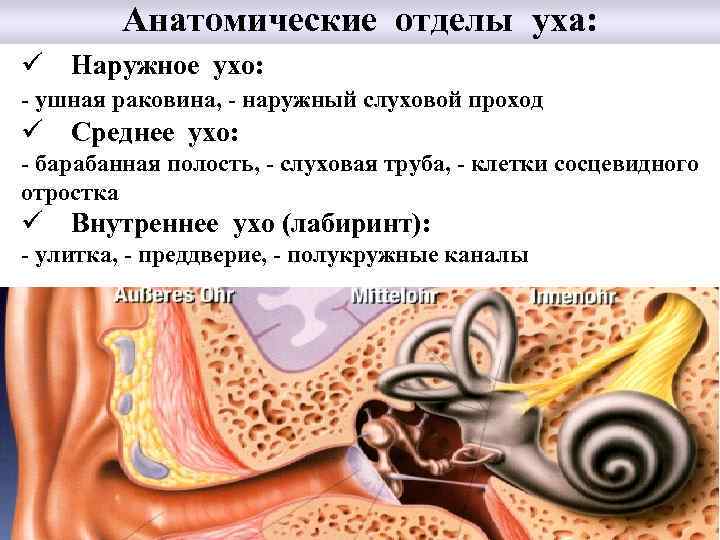

Анатомические отделы уха: ü Наружное ухо: - ушная раковина, - наружный слуховой проход ü Среднее ухо: - барабанная полость, - слуховая труба, - клетки сосцевидного отростка ü Внутреннее ухо (лабиринт): - улитка, - преддверие, - полукружные каналы